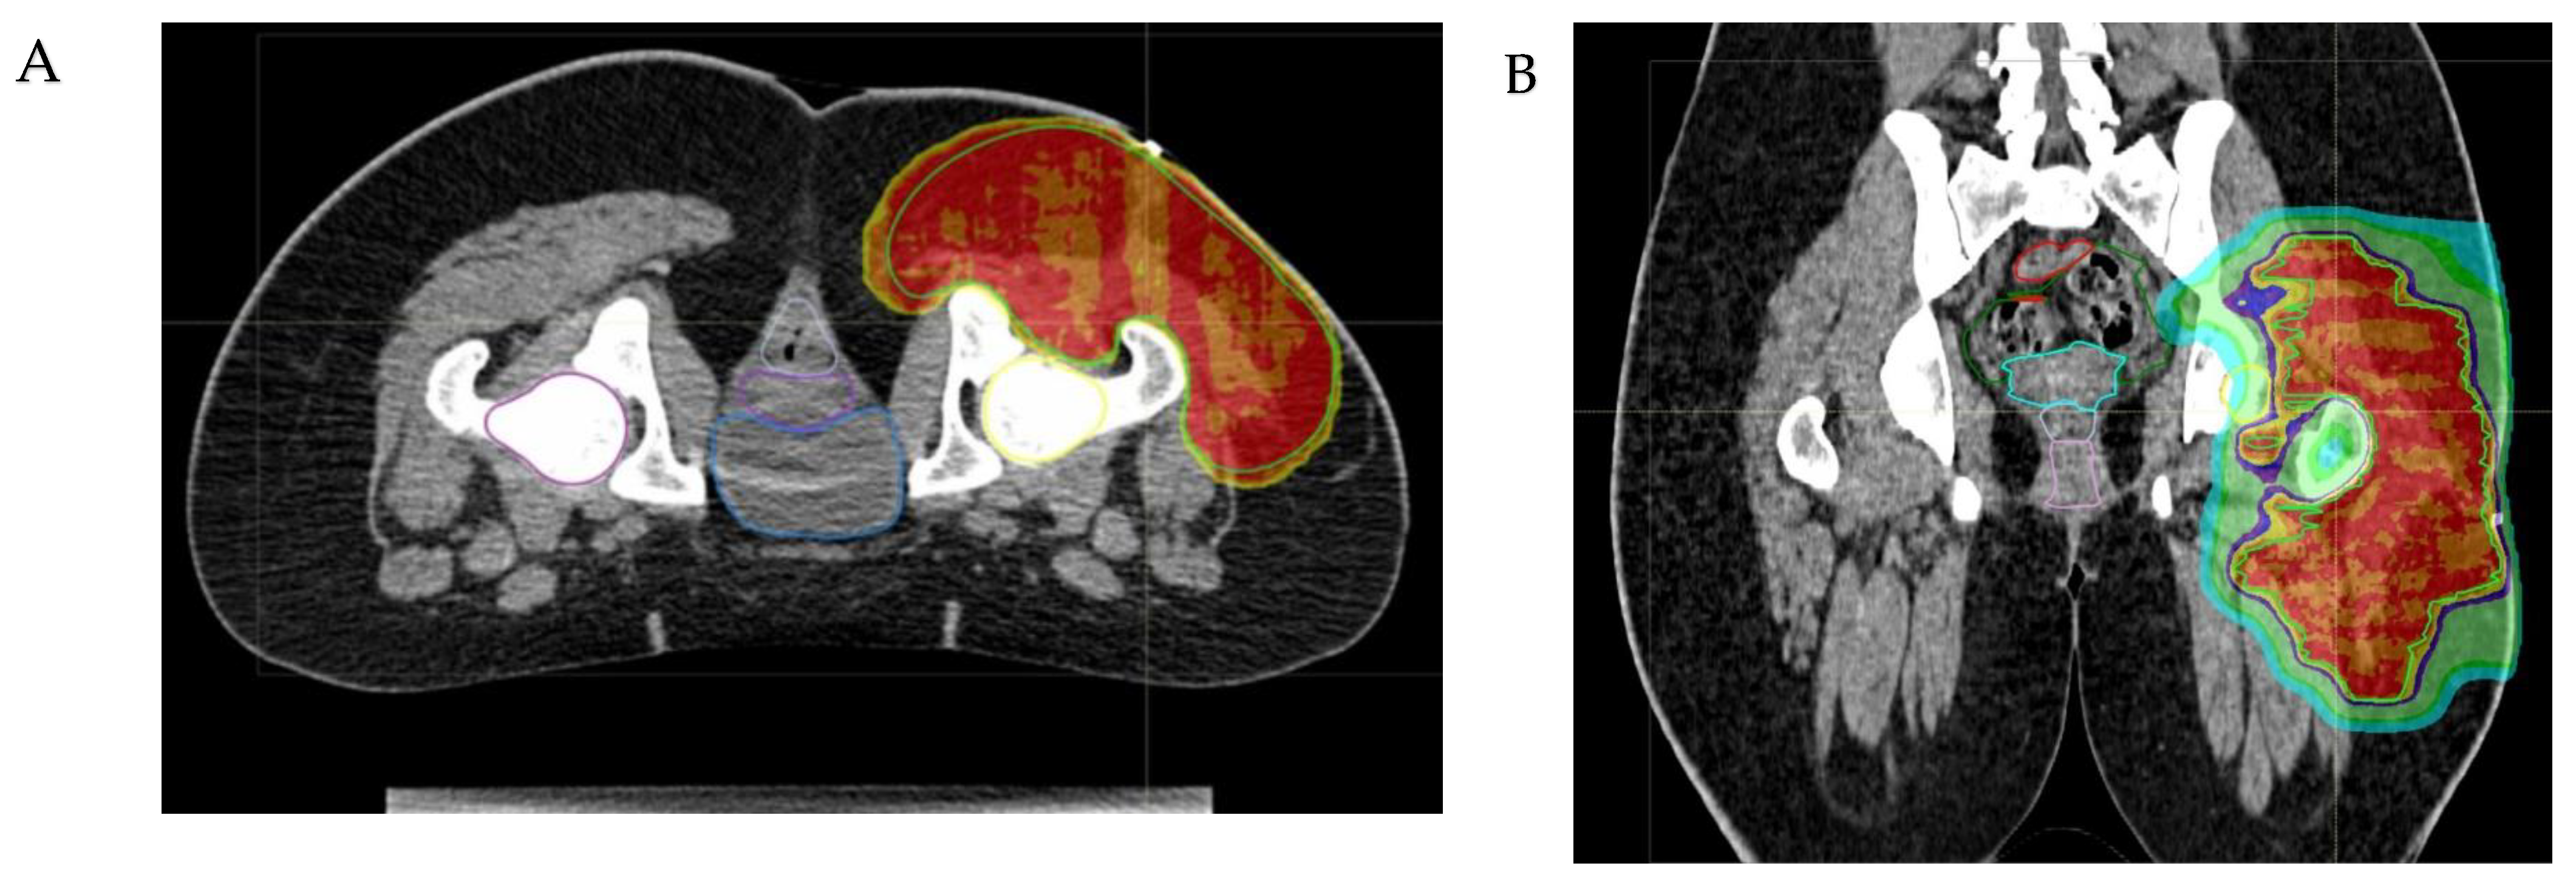

Figure 3.

The axial (A) and coronal (B) views of a proton beam plan illustrate the treatment of a malignant peripheral nerve sheath tumor (MPNST) in a 15-year-old girl, using a pencil-scanning proton beam therapy (PBS-PBT) technique. The images demonstrate the optimal coverage of the clinical target volume (CTV) by the high radiotherapy doses (isodoses of 100%, 98% and 95% of the prescribed dose, respectively indicated in red, orange and yellow), and the total sparing of the abdominal–pelvic risk organs, including the reproductive organs.

- The physical properties of protons allow for a significant escalation in dose, potentially up to approximately 60 Gy Relative Biological Effectiveness (RBE), in the treatment of radioresistant histotypes, such as Malignant Peripheral Nerve Sheath Tumors (MPNSTs) (see Figure 3).